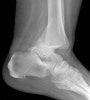

X-ray : 발목 관절 탈구(Ankle dislocation)

AP, lateral, Mortise view를 보면 대부분의 골절과 탈구가 진단됩니다.